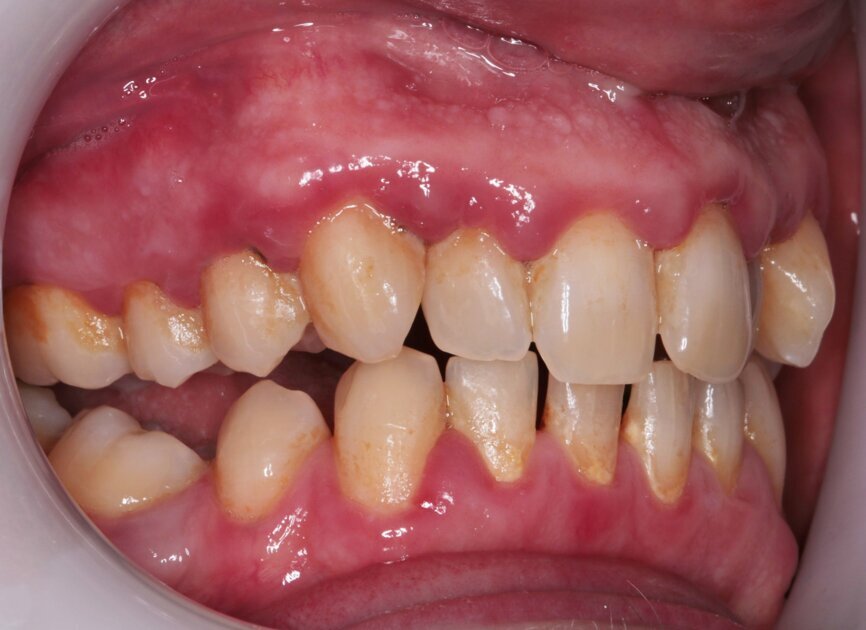

Fig. 3: Pre treatment left lateral

Fig. 4: Pre-treatment right lateral